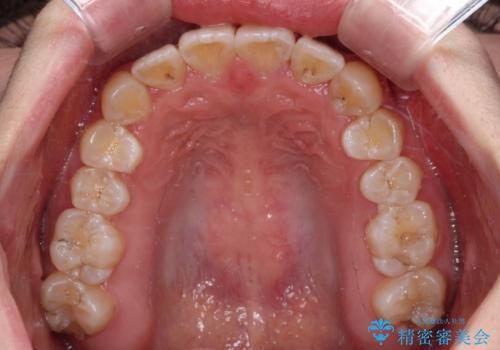

- 前歯のデコボコと八重歯を気にして来院された患者様です。

インビザラインでの治療を希望されていましたが、前歯のクロスバイトや下顎小臼歯の捻転が認められたため、インビザライン単独で治療を行うよりも、ワイヤー装置を併用した方が、治療期間の短縮やトラブル回避できると判断し、ワイヤー装置を併用することとしました。

まずはワイヤー装置により前歯のクロスバイトと下顎小臼歯の捻転を改善し、その後インビザラインにより全体を整える矯正治療を行うこととしました。